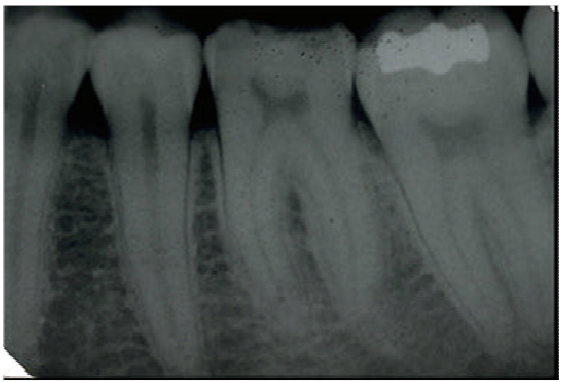

69.下圖下顎後牙區根尖片所顯示之左下第一大臼齒牙髓腔附近的放射線不透過性 (radiopaque)影像,最可能之診斷為何?

(A)牙髓腔結石(pulp stone) (B)牙骨質增殖(hypercementosis) (C)多生牙(supernumerary tooth) (D)牙釉質珠(enamel pearl)